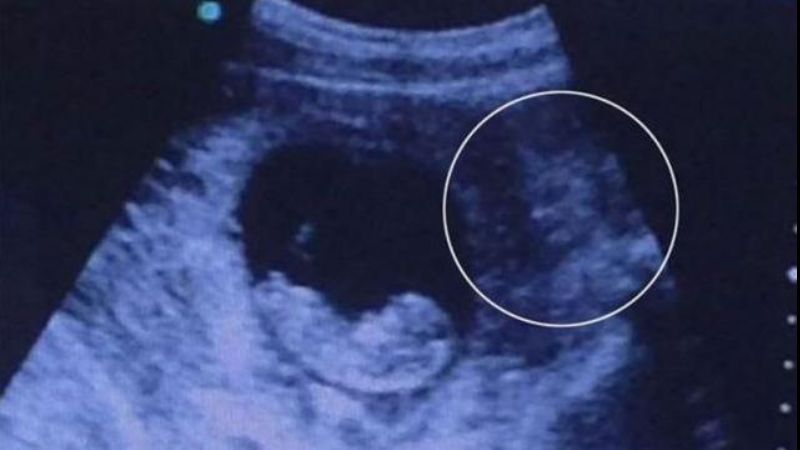

Es furor en las redes sociales la imagen de una ecografía que muestra ¿un demonio?

Una persona compartió "la ecografía de una amiga" en una popular red social y estalló la discusión: ¿Qué es lo que se puede ver al lado del feto?

Usuarios de las redes sociales se trenzaron en una discusión sobre una extraña forma que se puede divisar, en la placa de una ecografía que muestra el vientre de una mujer embarazada.

La polémica se relaciona con una extraña forma sombreada que se puede apreciar a la derecha de la imagen, sacando el foco sobre el bebé en gestación.

Las opiniones sobre la imagen publicada están divididas entre aquellos que creen que se trata de un demonio, una sirena o una representación de una diosa hindú.

No es la primera vez que la imagen del niño por nacer levanta la polémica entre las personas que creen en posesiones diabólicas, o en la presencia de fantasmas en este tipo de fotografías de ultrasonido.

La mamá que se realizó este estudio juró que la formación de la derecha, es el rostro de su padre, besando el feto que llevaba en el vientre.